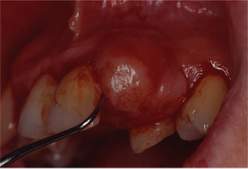

Fig. 7 e Fig. 8

Fasi dell'intervento per la rimozione chirurgica dell'epulide.

Fig. 11

Il tessuto osseo dopo la escissione dell'epulide.